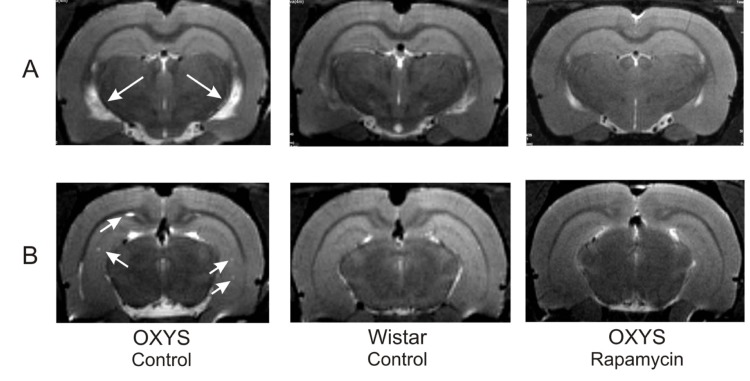

MRI revealed hydrocephalus in control group of OXYS rats (Table 1). The area of the lateral ventricles was about 2 times greater than that of Wistar rats (F1,10=17.12, p<0.002 in relative and F1,10=21.12, p<0.001 in absolute values). Rapamycin treatment eliminated the difference between rapamycin-treated OXYS and control Wistar rats in these parameters.

We had detected no loci of demyelination in the brain of Wistar rats. At the same time, 100% of OXYS rats from control group showed signs of neurodegeneration, which was manifested by loci of demyelination. Rapamycin supplementation decreased the percentage of animals with demyelination to 50±20% (F1,10=10.00, p<0.010). The number of loci in control OXYS rats was 4 times higher than in rapamycin-treated animals (F1,10=14.76, p<0.003).

Figure 6. MRI image of brain 4 month-old OXYS, Wistar rats and OXYS rats after rapamycin supplementation. (A) Hydrocephaly of lateral ventricle of OXYS rats (arrow). (B) Loci of demyelinization of the brain OXYS rats (arrow).

In agreement with our previous reports, here we described that 3-months-old OXYS rats displayed lower locomotor and exploration activities in the OF and a higher level of anxiety in the EPM tests in comparison with Wistar rats. Rapamycin treatment from the age of 1.5 months partially prevented the behavioral decline of OXYS rats. This improvement of behavior can be explained by normalization of the brain structure revealed by MRI. We demonstrated that rapamycin decreased the size of enlarged hypocampus, prevented hippocampal demyelination and decreased the volume of the lateral ventricles. Importantly, rapamycin abrogated hydrocephalus. It was shown that enlargement of ventricles is associated with accumulation of β-amyloid in the brain [44]. However we observed neither accumulation of β-amyloid nor effect of rapamycin. Instead, rapamycin decreased Tau phosphorylation, which was increased in control OXYS rats compared with Wistar rats. Noteworthy, rapamycin treatment decreased Tau phosphorylation in both rat strains. Tau is a microtubule-associated protein, which is widely expressed in neurons [45]. An increase of Tau phosphorylation and aggregation is toxic for neurons, causing nurodegeneration [46-49]. Also, tau phosphorylation impairs presynaptic function in hypertriglyceridemic mice [50].